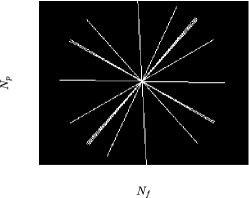

MRI data ( denotes the set of all complex-valued numbers) are observed in k-space (frequency domain), which spans an area of size (cf. Figs. 1a and 1b), with standing for the number of phase-encoding lines and for the number of frequency-encoding ones [1]. Data can be considered as the two-dimensional (discrete) Fourier transform of the image-domain data , i.e., [1]. Without any loss of generality, this study assumes that the “low-frequency” part of is located around the center of the area. Availability of the data over the whole k-space is infeasible in practice; k-space is usually severely under-sampled [3]. There exist several strategies to sample the k-space; examples are the 1-D Cartesian (Fig. 1a) and the radial (Fig. 1b) ones, where the “white” lines in Figs. 1a and 1b denote the available/sampled data, while data in the “black” areas are not observed. A general trend among sampling strategies is to put more emphasis on low-frequency components, which carry contrast information and with high SNR, and select few high-frequency components, which comprise high-resolution image details. The 1-D Cartesian sampling pattern emulates the acquisition of k-space pixels via the 1-D Gaussian distribution, acquiring a large number of samples in the central k-space area while sampling few ones from the “high-frequency” area (cf. Fig. 1a). The radial-sampling pattern consists of radial spokes which yield dense sampling at the center of k-space, while the sampling density is decreased as the spokes move away from the center (cf. Fig. 1b).

The proposed framework is validated over a range of undersampling/acceleration rates, defined by . 1-D Cartesian (Fig. 1a) as well as radial (Fig. 1b) sampling were applied to both the phantom datasets. To save space, only the 1-D Cartesian-sampling results are demonstrated for the MRXCAT dataset, while radial-sampling ones are shown for the phantom generated using real MR scans. Nevertheless, BiLMDM’s performance against the competing reconstruction algorithms follows a similar trend also for sampling strategies not included in the manuscript due to space limitations.